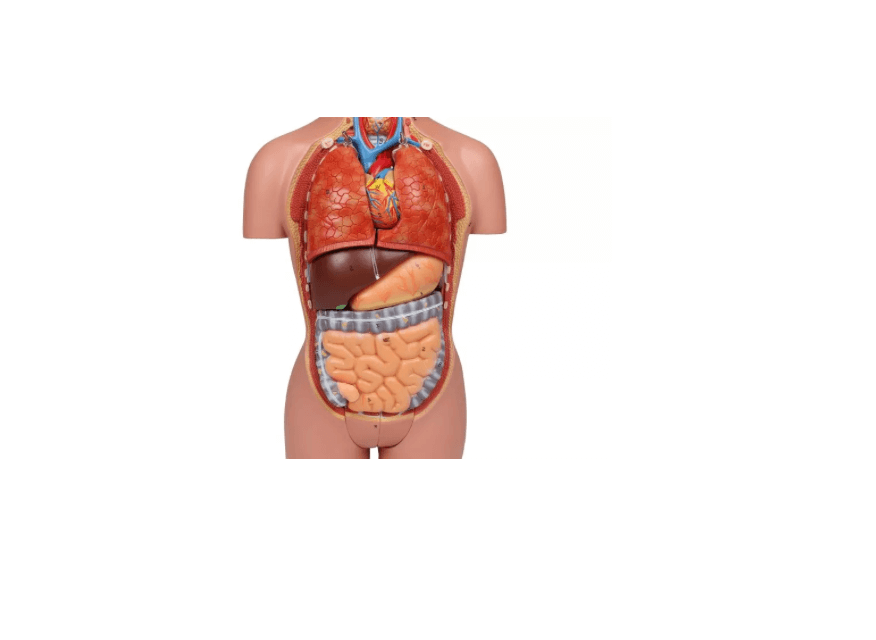

Dieses Torso-Modell in ca. ½ Lebensgröße bietet eine kompakte und dennoch äußerst detailreiche Darstellung der menschlichen Anatomie. Ideal geeignet als Schreibtischmodell, für den Anatomieunterricht oder zur Patientenaufklärung, vermittelt es anschaulich die Lage und den Aufbau innerer Organe – inklusive männlicher und weiblicher Geschlechtsorgane. Die verschiedenen Komponenten lassen sich entnehmen und untersuchen, was das Modell besonders nützlich für den Einstieg in die menschliche Anatomie macht. Lieferung erfolgt auf stabiler Grundplatte inklusive beschrifteter Anleitung.

Abnehmbare Organe – ideal zur Einzelbetrachtung

Modellteile im Überblick:

Grundkörper mit zwei Kopfhälften

Zwei Lungenhälften

Herz (zweiteilig zerlegbar)

Magen

Leber

Darmpaket mit abnehmbarem Blinddarmdeckel

Weibliche Geschlechtsorgane (zweiteilig)

Männliche Geschlechtsorgane (zweiteilig)